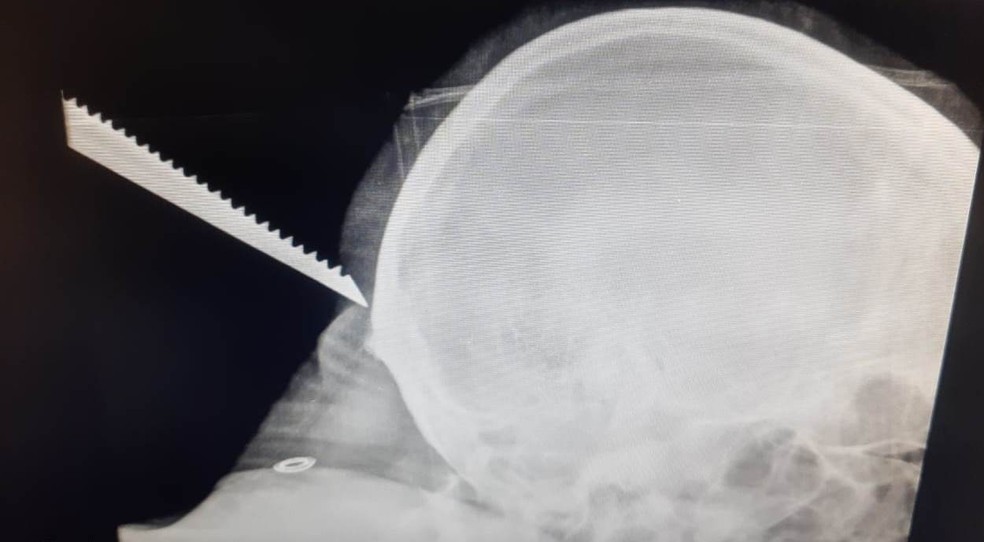

Um homem de 39 anos quase morreu após ter a nuca perfurada por uma serra. O acidente aconteceu nesta quarta-feira (8), em Mairinque, São Paulo.

A prefeitura do município afirmou o homem estava trabalhando quando acabou escorregando e caindo de costas no local onde estava a serra.

Ele foi socorrido e levado para um hospital ainda com a faca cravada, no entanto, foi constatado que, por sorte, não houve contato ou danificação da área do crânio.